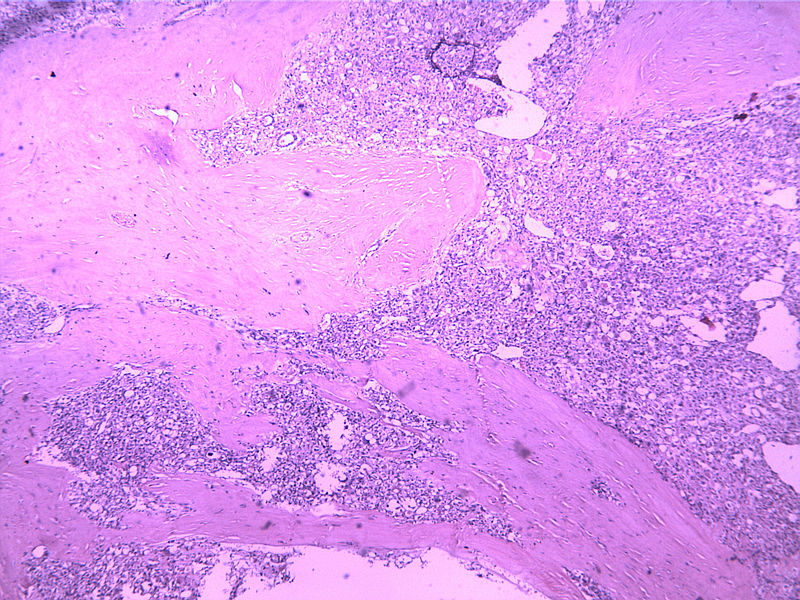

女30Y,大腿肿物5Y,直径3cm

年龄,部位,组织学形态均符合腺泡状软组织肉瘤,主要的鉴别诊断是副节瘤。

镜下见不典型脂肪细胞,结构不清,有侵袭现象,病理性核分裂现象多见,核距边。怀疑脂肪肉瘤。